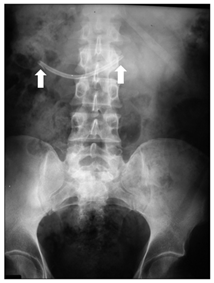

During the six years following laparoscopic cholecystectomy, the patient undergoes frequent medical examinations due to multiple episodes of acute cholangitis that require endoscopic dilatation of the stenosis and placement of biliary stents through endoscopic retrograde cholangiopancreatographies (ERCP) until, finally, the patient had a biliodigestive (Roux-en-Y) anastomosis. During surgery, the stent is not removed as it is not visualized and, based on the suspicion of a possible distal migration, a radiograph of the abdomen is requested, in which the prosthesis seems to be found in the hepatic angle of the colon (Figure 6). Over five months the patient was asymptomatic, and the stent, presumably in transit, was controlled through radiographs but it does not seem to change its location. In view of the above, it is decided to perform a computerized tomography to accurately locate the prosthesis (Figures 7-8), it was shown that it was located in the duodenum with the distal end in the region of the jejunal anatomy, since it had not managed to circumvent the angulation that occurs in the efferent jejunal loop just after the anastomosis.

Figure 6 Abdominal radiography shows the displaced stent (arrows).

Stent migration is considered a rare event, occurring in 5-10% of malignant processes, and with higher incidence in benign processes due to inflammation,9,12,13 as in our patient. In addition, migration has been reported to be more frequent with plastic prostheses,11 used in benign stenosis, as in this patient (Figure 7). Distally migrated stents normally pass through the gastrointestinal tract (86% of cases).10,14,15,16 For this reason, initial management for the patient was expectant, with thorough and prolonged follow-up by abdominal x-rays17 ( Figure 6). A lower percentage of prostheses remain in the intestine without symptoms10,14,15,16 as in the presented case. Thus, after a 5-month follow-up with abdominal x-rays, where no significant changes were observed in the location of the prosthesis, it was decided to perform an abdominal CT scan, both to locate the stent and to provide the endoscopist with detailed information of the abnormal post-surgical anatomy of the patient's upper gastrointestinal tract.23 Lastly, the prosthesis was localized in the duodenum with its distal end in the area of jejunojejunal anastomosis (Figure 8). We understand that at the beginning of the surgical Roux-en-Y hepaticojejunostomy there was a migration of the prosthesis, which remained in the duodenum until the end of the procedure. Subsequently, due to the angle in the segment of the anastomosis, the prosthesis failed to progress through this area remaining in the same location during the five months of follow-up (Figure 9).